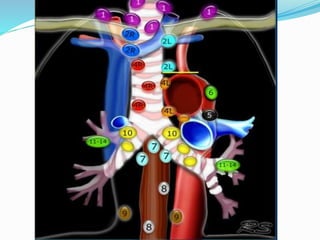

The International Association for the

 14 LN stations reorganized into 7 zones

 Supraclavicular zone

 Upper zone

 AP zone

 Subcarinal zone

 Lower zone

 Hilar zone

 Peripheral zone

Lymph nodal stations in ca lung